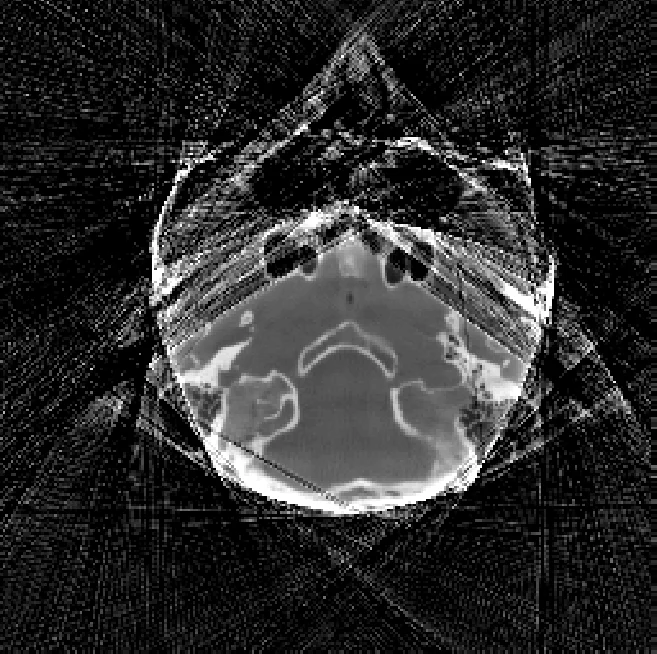

Second, they apply the method to CT reconstruction. A knee phantom is simulated with 360° projections; a subset of projections is artificially saturated to mimic over‑exposure. They compare three approaches: (a) conventional filtered back‑projection (FBP) on saturated data, (b) an extrapolation method based on fitting cylindrical shapes (state‑of‑the‑art), and (c) the proposed M1bit‑CS reconstruction. Visual inspection reveals that the extrapolation method reduces streaking but leaves noticeable “capping” artifacts (flattened HU values near the periphery). In contrast, M1bit‑CS effectively suppresses both streaks and caps, yielding images that closely resemble the ground‑truth unsaturated reconstruction. Quantitatively, mean absolute error (MAE) and structural similarity index (SSIM) improve by roughly 30 %–40 % over the extrapolation baseline, and the recovered Hounsfield Unit (HU) values in high‑density regions are much more accurate.

A second test on a simulated clinical head image confirms the findings: M1bit‑CS restores fine anatomical details obscured by saturation and reduces artifact intensity without requiring any prior geometric model of the object.